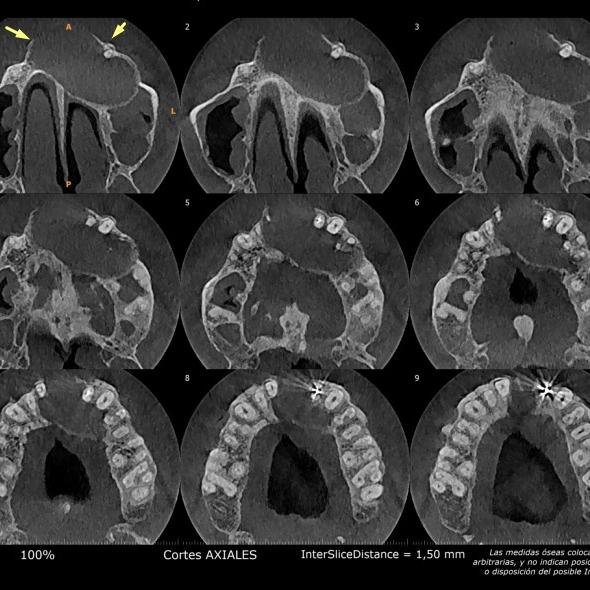

La presentación de casos radiográficos, permite la visualización de patologías que son muy difíciles de ver en la clínica, ya que muchos de ellos son hallazgos radiográficos. Además permite ver y refrescar clasificaciones y conceptos muchas veces estudiados. La presentación de los mismos no incluyen datos personales, mas que edad y sexo, que suelen ser importantes para ver la correlación entre la patología, su aparición o forma de presentación.